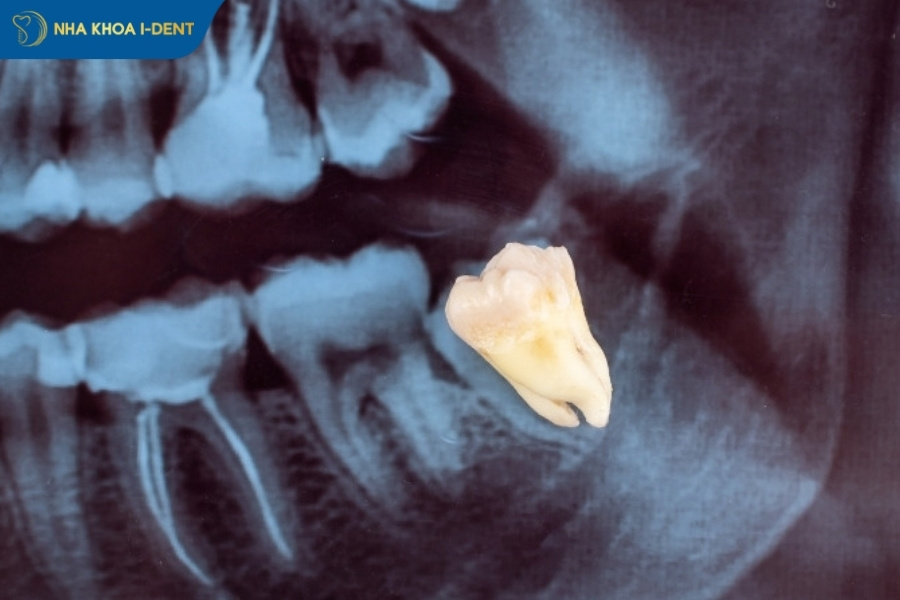

Có, răng khôn mọc lệch nhưng không đau vẫn nên nhổ để ngăn chặn các biến chứng âm thầm có thể phá hủy cấu trúc răng miệng từ bên trong. Nhiều trường hợp bệnh nhân không cảm thấy đau đớn nhưng khi chụp X-quang, răng khôn đã đâm thủng chân răng số 7 hoặc gây tiêu xương diện rộng.

- Bước 1: Bác sĩ sẽ tiến hành thăm khám, đánh giá tổng quát sức khỏe răng miệng, chụp phim để xác định hướng mọc và vị trí của chân răng so với dây thần kinh.